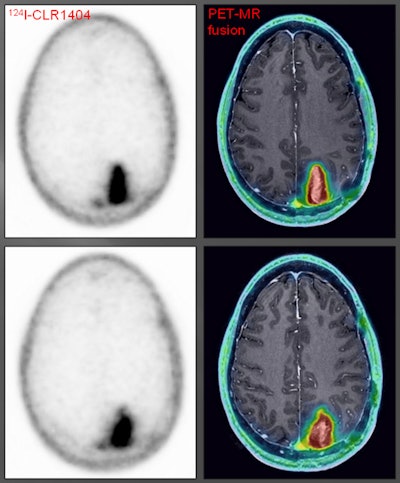

A patient with a grade III glioma was scanned using an iodine-124 (I-124) CLR1404 radiopharmaceutical. PET with CLR1404 detected the cancer, and fused PET/MRI delineated the tumor. Images courtesy of Dr. Lance Hall and the University of Wisconsin's UW Health. To learn more, go to bit.ly/1svWnOC.